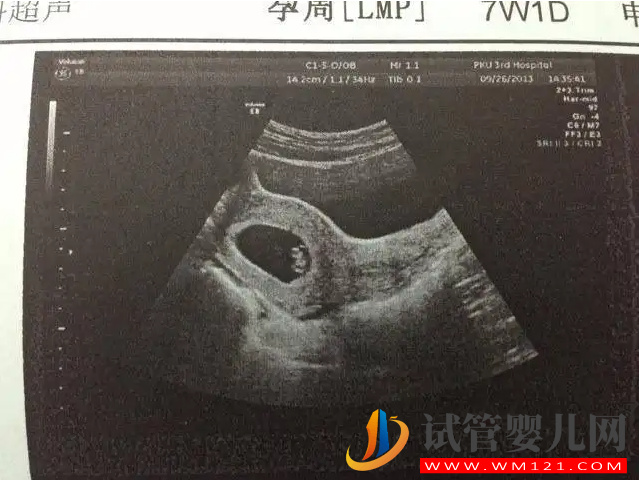

- 孕7周:胎兒長到1.33cm左右,在B超下可以清楚看到胎芽及胎心跳,孕囊約占宮腔的l/3;

懷孕50天大約處于懷孕的第7周至第8周的過渡階段,這個時候胎兒可能在1.33cm-1.66cm左右的樣子,已經(jīng)逐漸的形成了胎兒形狀,體節(jié)已全部分化,四肢分出,各系統(tǒng)進一步發(fā)育。